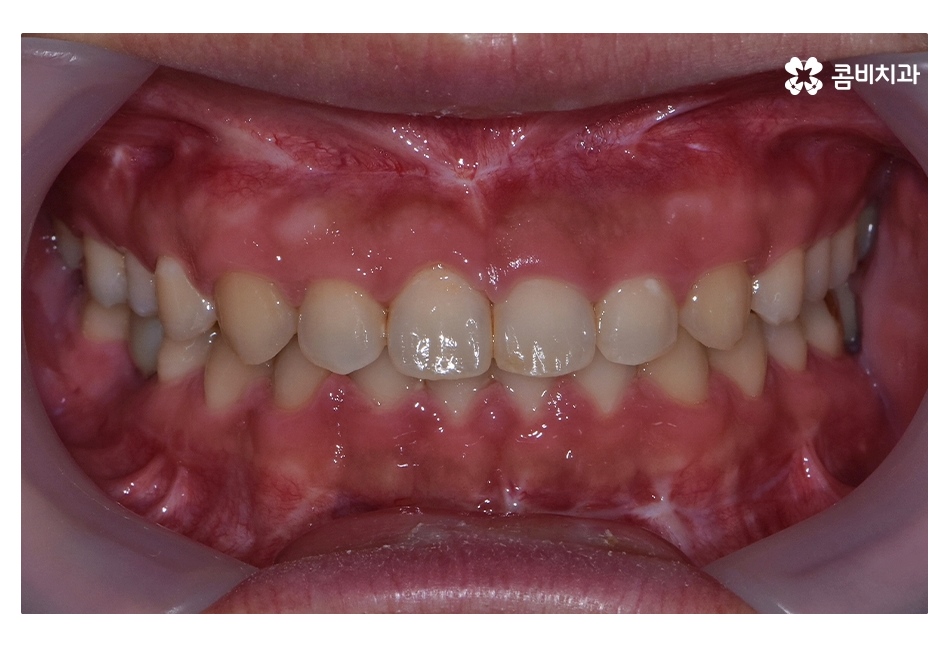

오늘 보시는 사례는 아랫니가 윗니를 덮고 있는

반대교합의 상태로 음식을 제대로 씹지 못하고

발음이 부정확하며 심미적으로도 좋지 않기 때문에

치아교정을 통해 치료가 필요한 케이스 중 하나라고 볼 수 있어요

클리피씨교정이 진행되고 시간이 지날수록 아랫니가

점점 윗니에 덮이는 정상 교합의 상태로 개선되는 것을 볼 수 있는데요.

치아교정은 개인에 따라서 치료 기간이 달라지겠지만

위 환자분의 경우 수술과 병행되어 비발치 교정으로 진행되었기 때문에

약 1년 6개월 정도의 기간이 소요되었으며

교정 후 교합이 정상적으로 맞물리는 것을 확인할 수 있어요.